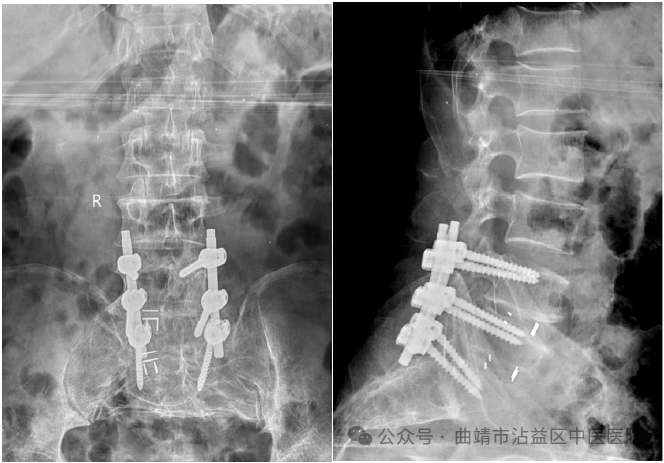

患者马某,男,56岁,因“右下肢反复麻木疼痛半年余”至沾益区中医医院就诊,收入我院骨伤科。入院后查体:右下肢麻木疼痛至足趾尖部,右下肢活动受限,右下肢直腿抬高试验阳性。患者手术指征明确,无明显手术禁忌,征得患者家属同意后,骨伤科医师团队决定为患者行L4-5;L5-S1椎间盘切除+椎间融合术,L4-S1钉棒系统内固定术。手术如期进行,在骨伤科医师团队的操作下,为患者顺利实施了椎间盘切除+椎间融合术。术后患者恢复良好,麻木疼痛感消失,3天即可下床活动。

此手术为沾益区范围所属医院第一例由本院医生独立完成的手术,同时也填补了沾益区此项医疗技术的空白。